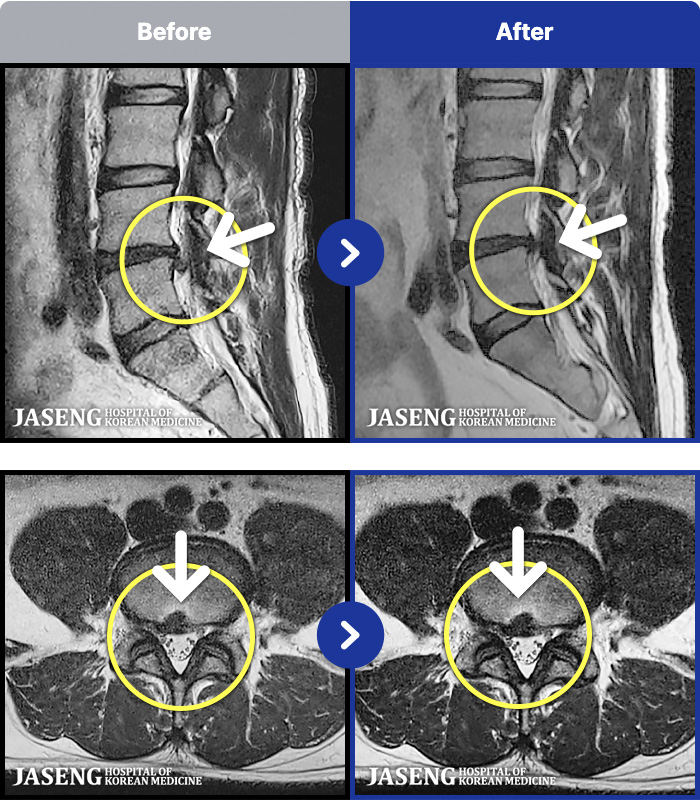

MRI ũ ʸ Ȯϼ.